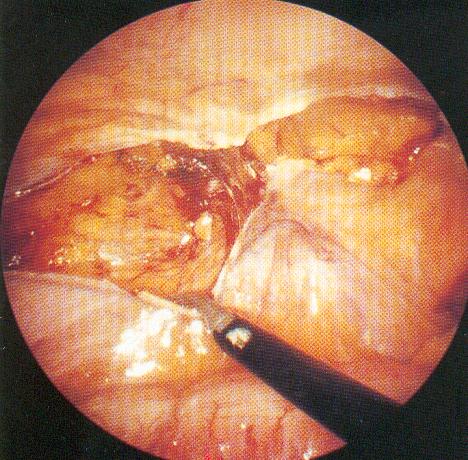

Βέβαια δεν πρέπει να ξεχνάμε ότι ναι μεν η μέθοδος της λαπαροσκόπησης είναι ο καλύτερη μέθοδος για την αντιμετώπιση ασθενειών και προβλημάτων, αλλά απαιτείται υψηλός βαθμός εκπαίδευσης και εμπειρίας από το χειρουργό που την εφαρμόζει δε.